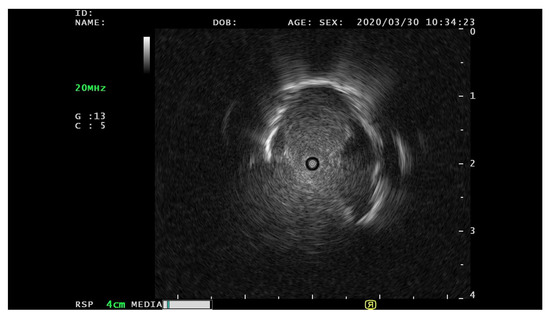

3.1. Data Pre-Processing